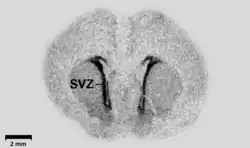

The subventricular zone (SVZ) is a region situated on the outside wall of each lateral ventricle of the vertebrate brain.[2] It is present in both the embryonic and adult brain. In embryonic life, the SVZ refers to a secondary proliferative zone containing neural progenitor cells, which divide to produce neurons in the process of neurogenesis.[3] The primary neural stem cells of the brain and spinal cord, termed radial glial cells, instead reside in the ventricular zone (VZ) (so-called because the VZ lines the inside of the developing ventricles).[4]

In the developing cerebral cortex, which resides in the dorsal telencephalon, the SVZ and VZ are transient tissues that do not exist in the adult.[4] However, the SVZ of the ventral telencephalon persists throughout life. The adult SVZ is composed of four distinct layers[5] of variable thickness and cell density as well as cellular composition. Along with the dentate gyrus of the hippocampus, the SVZ is one of two places where neurogenesis has been found to occur in the adult mammalian brain.[6] Adult SVZ neurogenesis takes the form of neuroblast precursors of interneurons that migrate to the olfactory bulb through the rostral migratory stream. The SVZ also appears to be involved in the generation of astrocytes following a brain injury.[7]